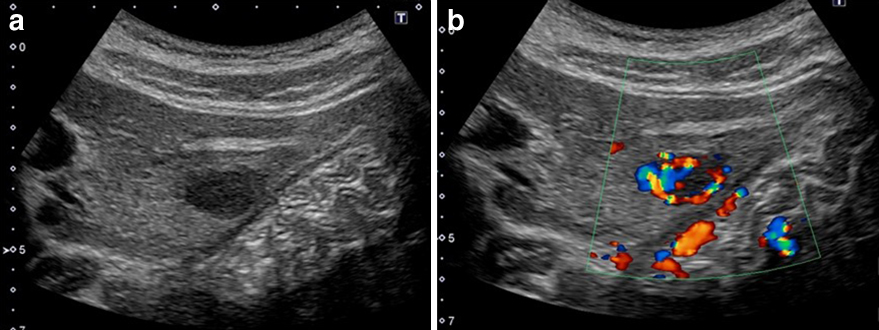

腹部超音波検査所見:肝S2に2.1×1.8 cm大の低エコー腫瘤があり,境界明瞭粗造で内部不均一,後方エコーは不変であった(Fig. 1).また,カラードプラではhypervascularであった.

Abdominal US showed a well-demarcated hypoechoic tumor 20 mm in diameter in segment 2 of the left lobe (a). Color doppler US indicated hypervascularity of the tumor (b).